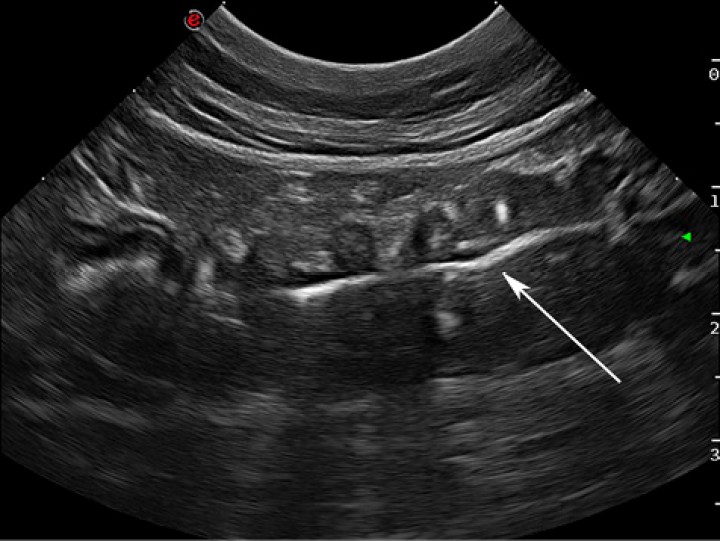

Se procedió a realizar una ecografía de abdomen donde se observó un tramo del yeyuno plicado, que mantenía la estratificación de las capas y en cuyo interior se visualizó una estructura hiperecogénica que proyectaba una sombra acústica tenue (Fig. 3; Vídeo 1). No se apreciaron alteraciones ecográficas evidentes en el resto de los órganos abdominales evaluados, ni tampoco se observaron anomalías a nivel de peritoneo u omento, ni presencia de linfadenopatías.

<p>Imagen ecográfica de una asa de intestino delgado. Se visualiza el intestino plicado y en el interior una línea hiperecogénica consistente con un cuerpo extraño lineal (flecha blanca).</p>

Imagen ecográfica de una asa de intestino delgado. Se visualiza el intestino plicado y en el interior una línea hiperecogénica consistente con un cuerpo extraño lineal (flecha blanca).

Según los hallazgos radiológicos y ecográficos encontrados, el diagnóstico definitivo fue el de un cuerpo extraño lineal en intestino delgado.

En los pacientes que presentan una obstrucción intestinal mecánica debido a cuerpos extraños de cualquier tipo, tanto lineales como no lineales, las técnicas de diagnóstico por imagen son una herramienta fundamental para el diagnóstico.[ Agut A, Reyes A, Soler M. Signos radiográficos de la obstrucción intestinal mecánica. Canis et felis 2015; 136: 34-56. ] La técnica de imagen más utilizada en primer lugar suele ser la radiografía de abdomen, visualizándose en el caso de los cuerpos extraños lineales el patrón de plicación de las asas intestinales,[ Agut A, Reyes A, Soler M. Signos radiográficos de la obstrucción intestinal mecánica. Canis et felis 2015; 136: 34-56. , Riedesel A.R. Abdominal cavity: canine and feline. En Thrall D.E.(autor): Textbook of veterinary diagnostic radiology. 7ª edición. Missouri: Elsevier; 2017; 939 – 947. ] aunque en muchas ocasiones no llega a ser diagnóstica y necesitamos recurrir a la ecografía o a técnicas de contraste para obtener un diagnóstico más fiable.[ Agut A, Reyes A, Soler M. Signos radiográficos de la obstrucción intestinal mecánica. Canis et felis 2015; 136: 34-56. ] Actualmente, la ecografía suele ser la técnica de elección ante la realización de una técnica de contraste. En nuestro caso optamos por realizar una ecografía, visualizando el cuerpo extraño lineal como una estructura hiperecogénica en el interior de las asas intestinales afectadas con una sombra acústica tenue, aunque en ocasiones, dependiendo de las características del cuerpo extraño, puede que no se aprecie sombra acústica.[ Griffin, S. Feline abdominal ultrasonography: What’s normal? What’s abnormal? J Feline Med Surg 2019; 21: 1047-1060. [PubMed] ]